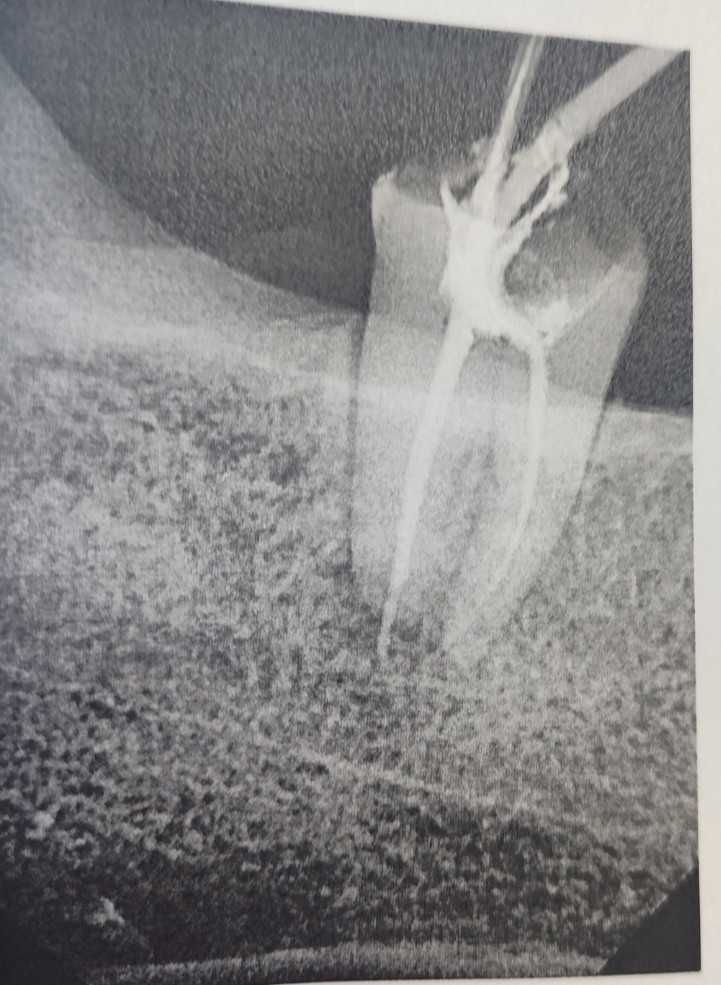

Болит, зуб мудрости, с право низ. Стоит постоянная пломбу. До, этого открывали и чистили каналы. Боль, сильная   с верху. Удалить, не хочу. Хочу сохранить. Полоскала содой. Что, делать? Помогите пожалуйста.... Есть, снимок, рентген

По снимку видно ранее проведённое лечение каналов, но при сохраняющейся сильной боли возможен воспалительный процесс. Для сохранения зуба требуется перелечивание у эндодонтиста с использованием микроскопа. Самолечение и полоскания не помогут поэтому рекомендую как можно скорее обратиться к врачу.